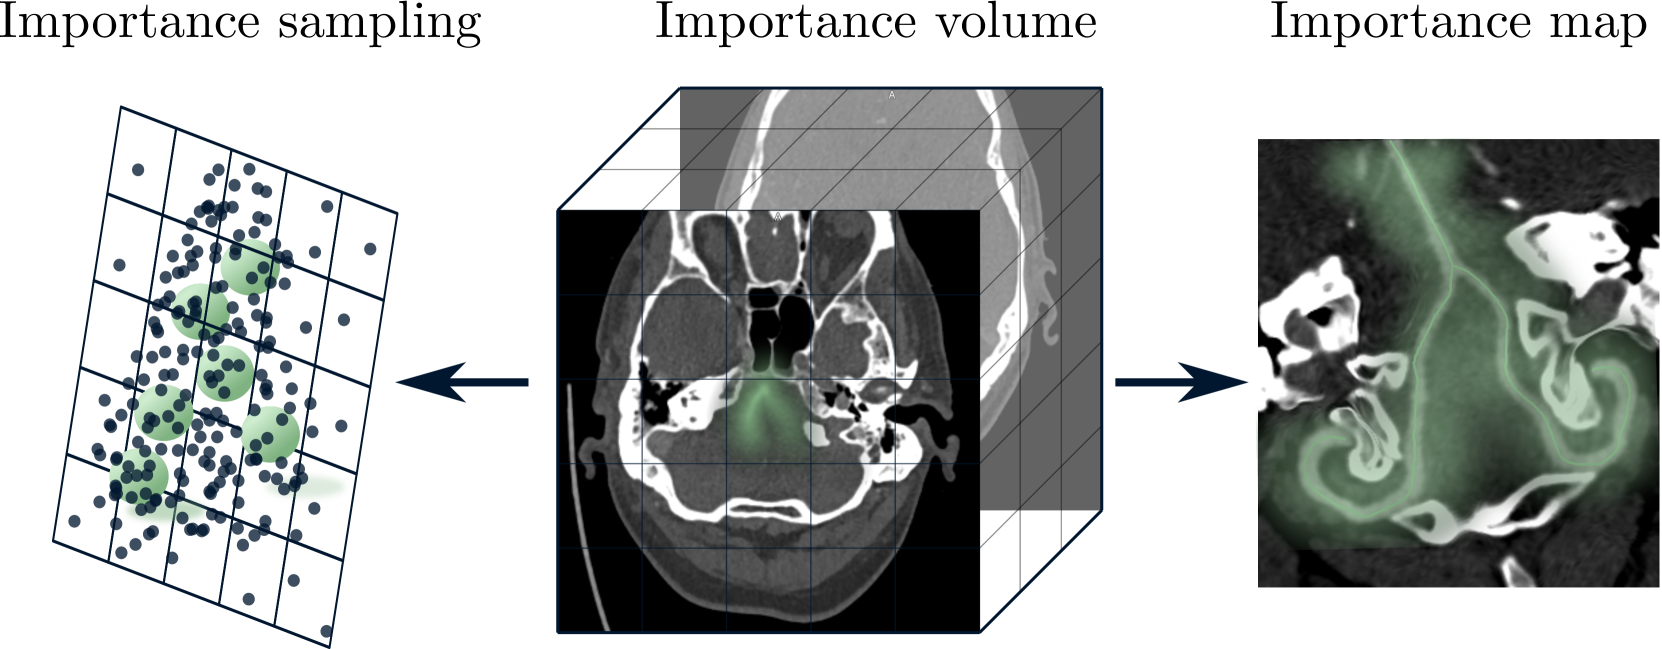

Refer to caption

Figure 3: Importance sampling (left) and map overlay (right) from an importance definition in volumetric space which is inversely proportional to the Euclidean distance to the target (green).

5.2 Importance Sampling & Map

Input sampling strategies for fitting neural fields in image registration include uniform [37] or downscaled (global) plus patchwise (local) schemes [34]. To accelerate fitting at relevant and more complex locations, we assign less importance to transformations distant to the targets. Proximity to target positions can be precalculated by applying the Euclidean Distance Transform e(I)𝑒𝐼e(I)italic_e ( italic_I ) to the volume grid. A volume of importance weights VE=|min(e(I)α,0)|+βα+βsubscript𝑉E𝑒𝐼𝛼0𝛽𝛼𝛽V_{\text{E}}=\frac{|\min(e(I)-\alpha,0)|+\beta}{\alpha+\beta}italic_V start_POSTSUBSCRIPT E end_POSTSUBSCRIPT = divide start_ARG | roman_min ( italic_e ( italic_I ) - italic_α , 0 ) | + italic_β end_ARG start_ARG italic_α + italic_β end_ARG inverts the distance map and clips values >>>α𝛼\alphaitalic_α, giving more weight to points close to the target while assigning a minimum value of β𝛽\betaitalic_β to the rest. Transforming a coarse input grid with the neural field and reading out VEsubscript𝑉EV_{\text{E}}italic_V start_POSTSUBSCRIPT E end_POSTSUBSCRIPT yields a 2D importance map E𝐸Eitalic_E, as shown in Fig. 3. We perform importance sampling by selecting points according to the distribution in E𝐸Eitalic_E, while ensuring coverage of all regions with β𝛽\betaitalic_β>>>00. Inspired by ADR [13], one can utilize the value of VE(𝐱^i)subscript𝑉Esubscript^𝐱𝑖V_{\text{E}}(\mathbf{\hat{x}}_{i})italic_V start_POSTSUBSCRIPT E end_POSTSUBSCRIPT ( over^ start_ARG bold_x end_ARG start_POSTSUBSCRIPT italic_i end_POSTSUBSCRIPT ) during model fitting as weighting factor wssubscript𝑤𝑠w_{s}italic_w start_POSTSUBSCRIPT italic_s end_POSTSUBSCRIPT in Eq. (4). This emphasizes small distortions close to the target and can help to move inevitable distortions to less important areas. We choose a fixed sampling size of 50k point pairs per epoch that are optimized in a single batch.

The influence on convergence of different sampling schemes (uniform-random, downsampled pretraining followed by patchwise fitting [34] and our importance sampling) is investigated using 500 samples for the first 500 epochs and is shown in Fig. 9 and Sup. Tab. 4. In early fitting stages, our oversampling of the target regions leads to more consistent centerline coverage (\approx 0.5 mm improvement on median target distance) with lower median distortion. In later stages, the effects become marginal compared to uniform-random. While downsampled pre-fitting results in a reasonable low-frequency approximation of the target vessels (e.g. 0.87 mm median distance in Fig. 9), the additional patch-wise sampling [34] does not converge to a meaningful solution for this task. We do not compare against sampling schemes that sample densely in regions with high error [10] as we intend to control the location of distortion.